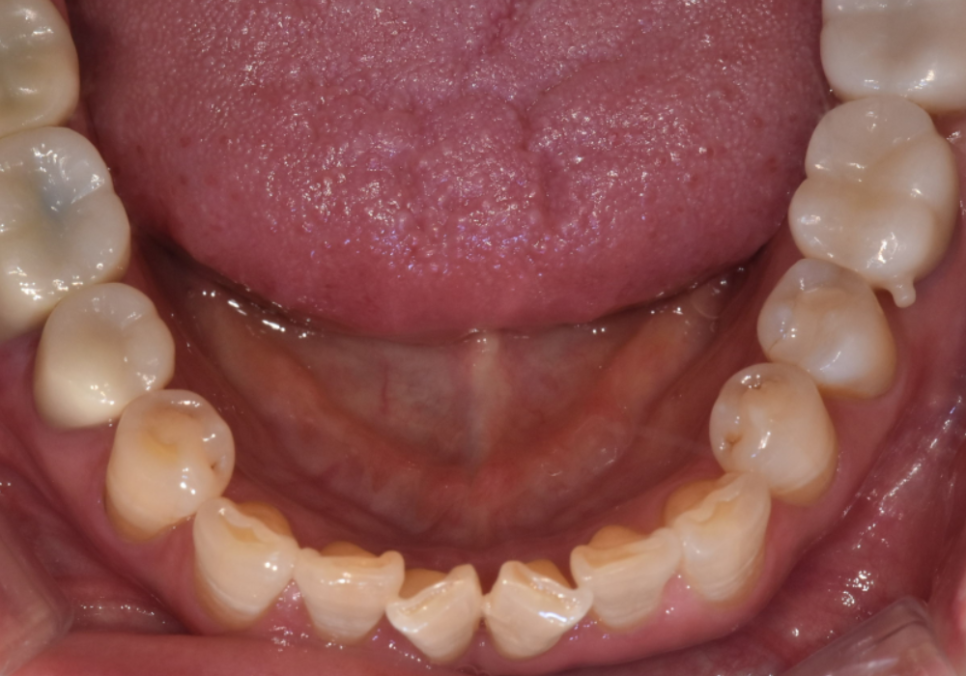

최근 아래 앞니가 나비 날개처럼 뻗어

고민이셨던 분이 찾아오셨습니다.

치아가 바깥으로 벌어져 있다 보니

평소 입술이 자꾸 걸리고

면 요리를 드실 때도 잘 끊기지 않아

무척 불편하셨다고 해요.

260102

환자분은 긴 교정 기간을 감당하기

어려운 상황이셨고,

이런 실생활의 불편함을

하루빨리 해결하길 원하셨죠.

물론 교정도 방법이겠지만,

현재의 구강 상태를

종합적으로 고려해 보았을 때,

전체적인 치아 배열은 안정적이라,

앞니를 많이 깎아내지 않고도

충분히 배열을 맞출 수 있는 상태였습니다.

전체 치아를 이동시키는 교정 대신,

틀어진 각도만 정교하게

바로잡는 라미네이트로 가닥을 잡았고,

결과적으로 환자분께

가장 만족스러운 대안이 되었습니다.